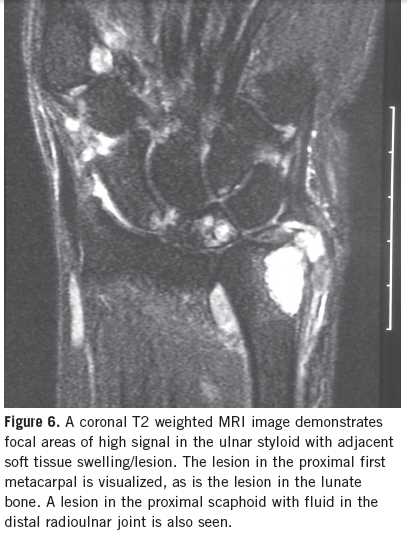

William Yaakob, MD

A 56-year-old white woman complains of wrist pain, primarily located in the right wrist but to a lesser degree in the left as well.